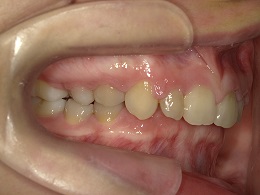

治療前左側

治療前右側